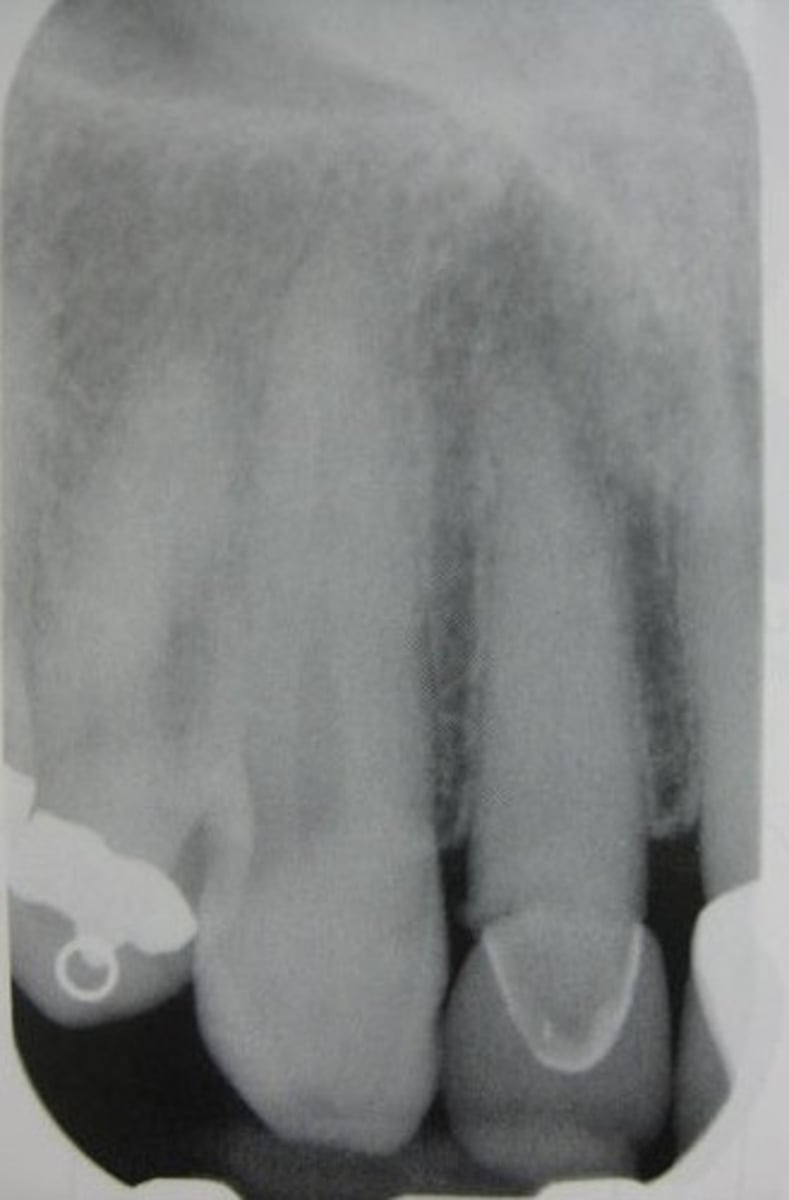

absence of apical structures

receptor not positioned to cover apical region of teeth

bite block not placed on the teeth being exposed

absence of apical root structure

dropped receptor corner